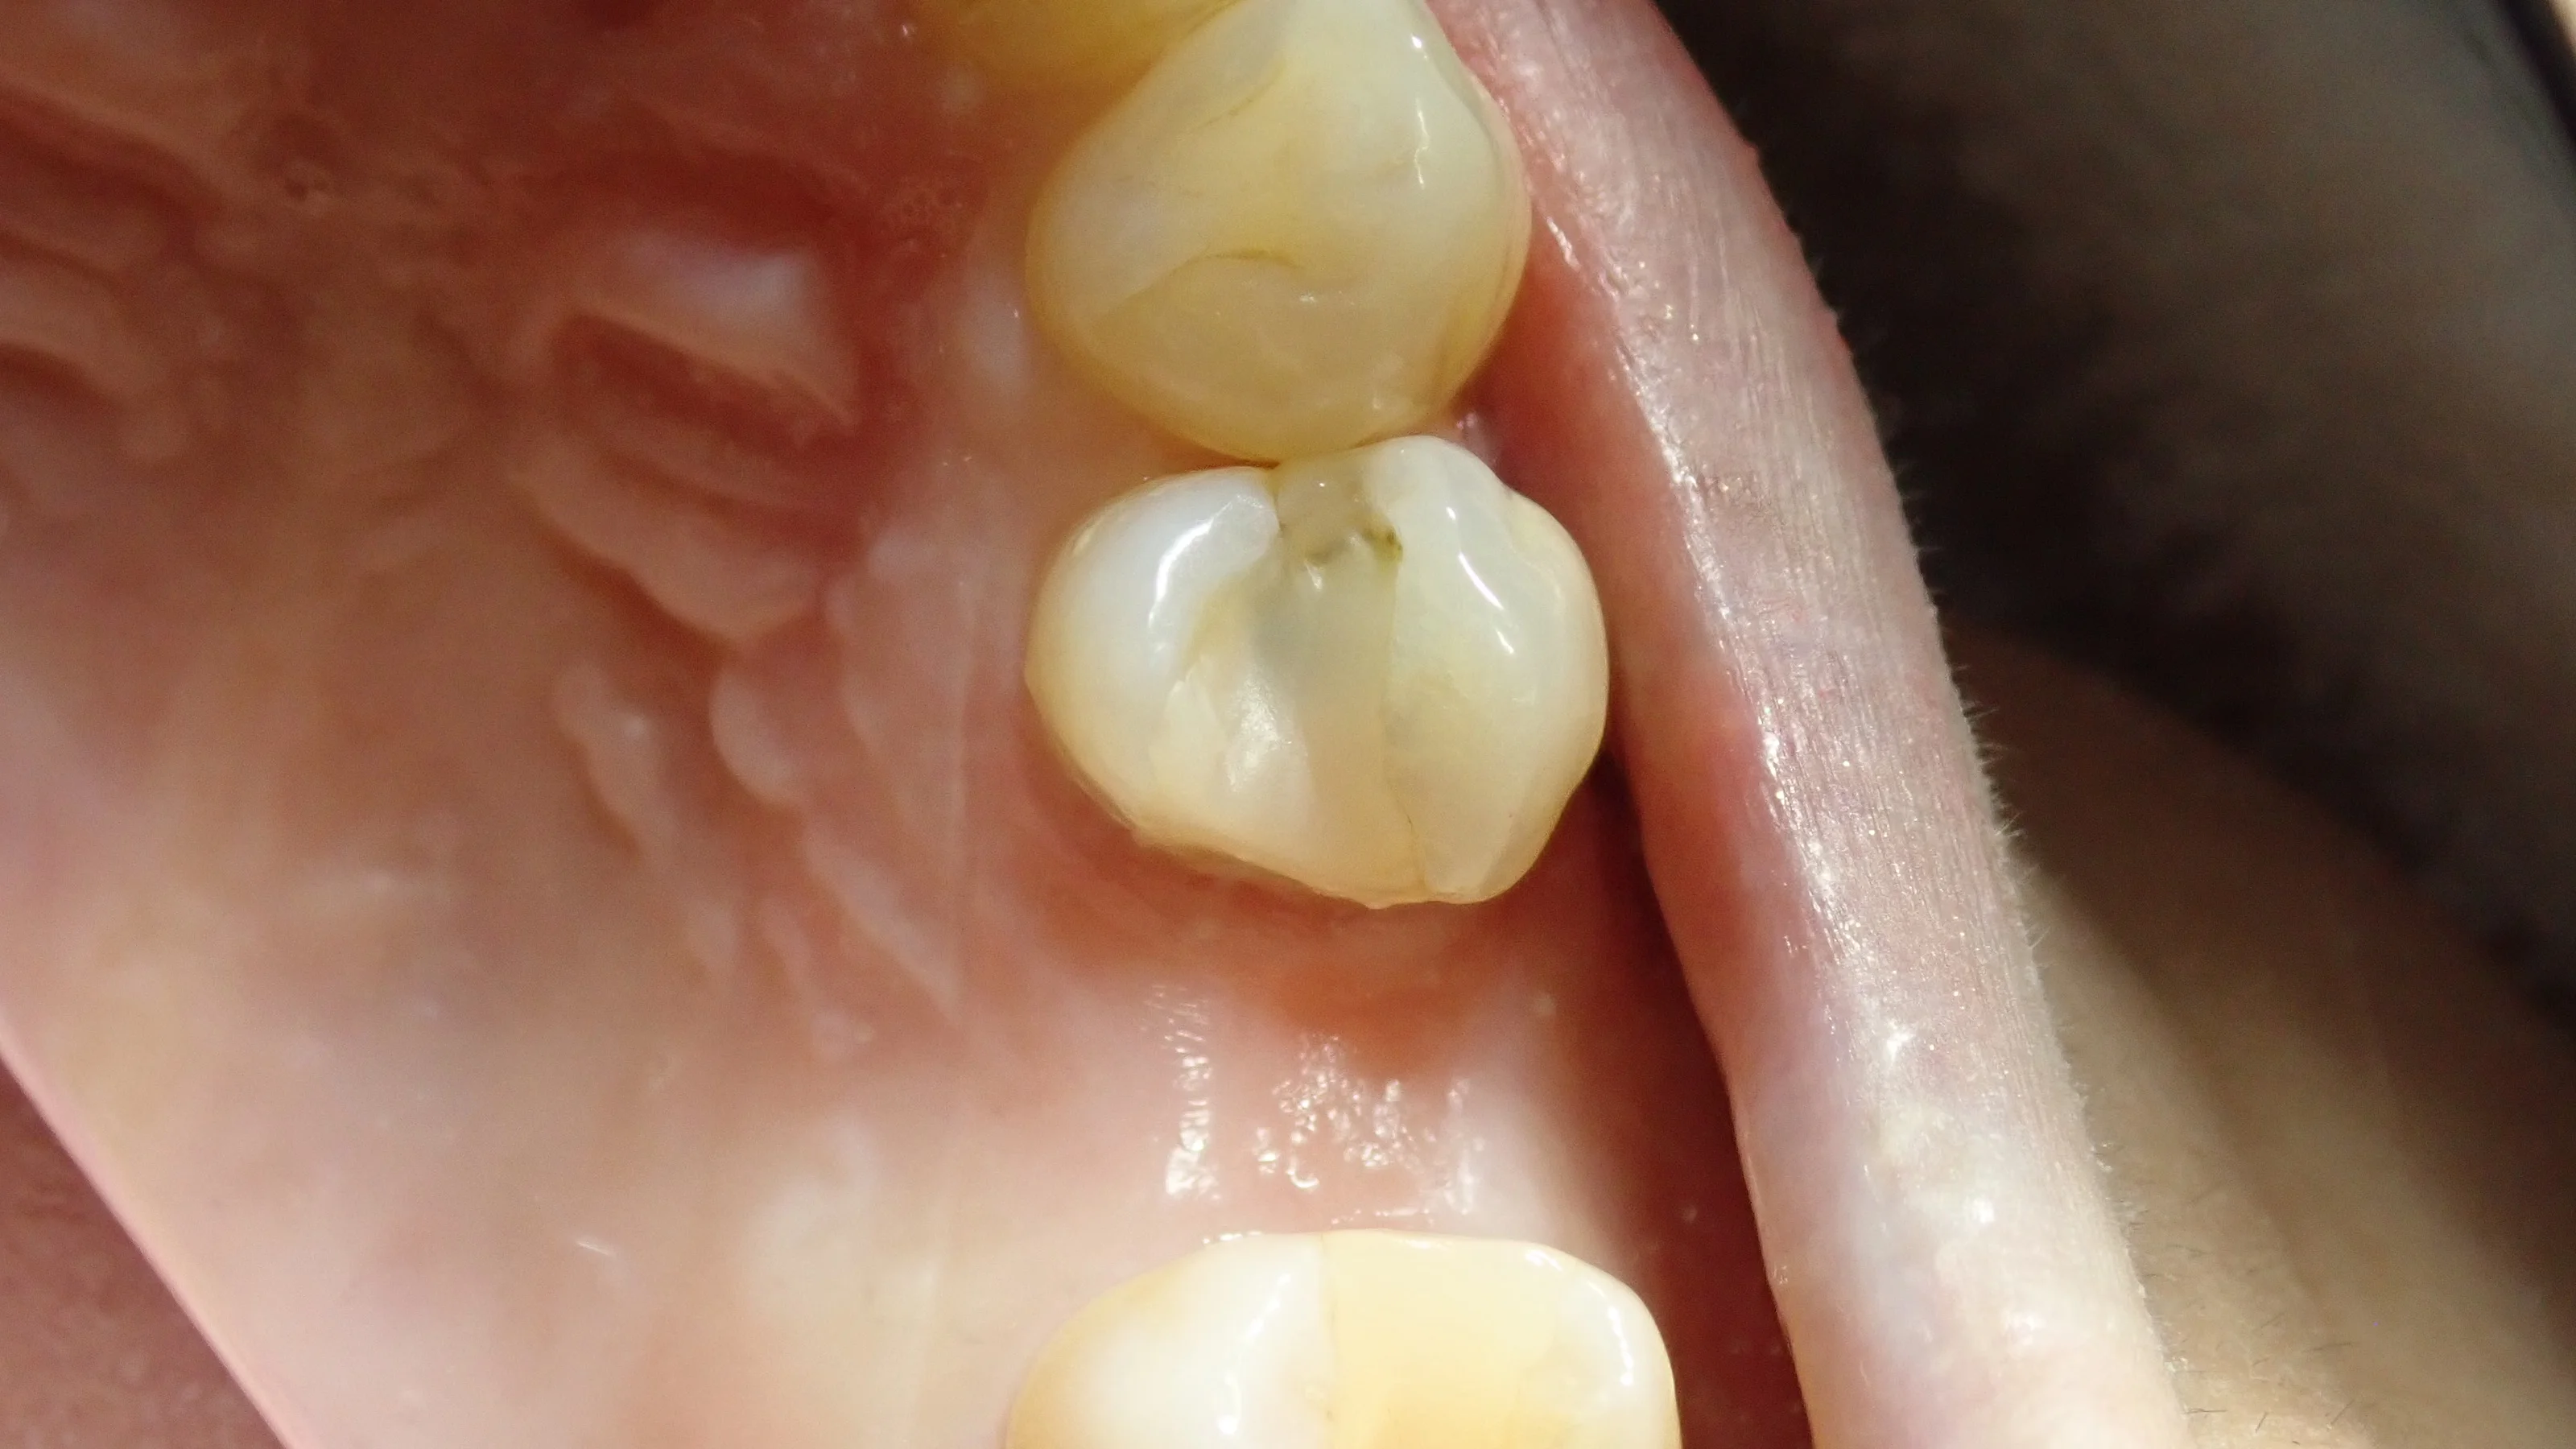

虫歯を取り切った状態がこちら。

・・・案の定、虫歯が神経まで行ってしまっていました。

神経が生きていれば、露出した段階で出血してきますが・・・神経のあるはずの場所を触ってみても全く出血せず。

確実に神経が死んでおり、神経の治療が必要である旨を説明し、同意を得たので、神経の治療へ。